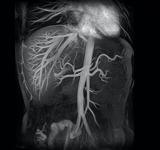

An example of a noncontrast MRA image from Toshiba.

The organization acquired a Vantage Atlas MR unit by Toshiba America Medical Systems Inc. The manufacturer developed the full suite of contrast-free MRA techniques available on the entire Vantage MR product line to combat adverse medical events such as NSF/NFD. These techniques include fresh blood imaging (FBI), contrast-free tmproved angiography (CIA), time-spatial labeling inversion pulse (time-SLIP) and time and space angiography (TSA).